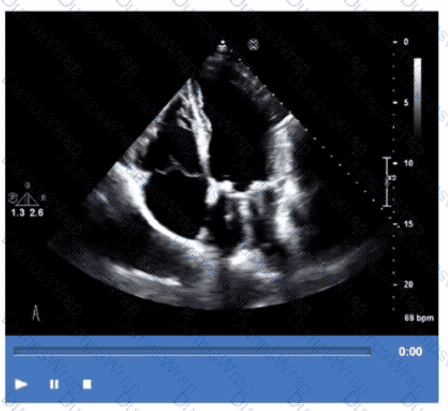

Which step is next in further evaluation of the abnormality shown in this video?

CExplanation:

Comprehensive and Detailed Explanation From Exact Extract:

The video suggests an atrial septal abnormality possibly a patent foramen ovale or interatrial shunt. To evaluate for right-to-left shunting across an atrial septal defect, the administration of agitated saline contrast with a Valsalva maneuver is the next best step.

Valsalva increases right atrial pressure transiently, promoting transient right-to-left shunting, making microbubbles visible in the left atrium if a shunt is present. Administration without Valsalva reduces sensitivity. The choice of arm vein (right or left) is less critical.

This diagnostic technique is well described in ASE adult congenital heart disease guidelines and echocardiography contrast protocols【12:ASE Contrast Echocardiography Guidelines†p.190-195】【16:Textbook of Clinical Echocardiography, 6e†p.575-580】.